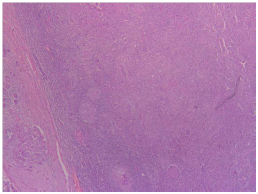

The pathology report revealed presence of lymphoepithelial carcinoma of the right parotid gland with positive lymph nodes from specimens taken. Upon performing pathological studies, the sample excised was stained with hematoxylin and eosin stain (Figure 3) which showed lymphocytic infiltrates invading the parotid gland, EBER stain (Figure 4) showed positive results for presence of Epstein bar virus. The excised lymph nodes were also stained (Figure 5), and metastasis was found.

Figure 3 Parotid gland with marked lymphocytic infiltrates (H & E, 4X).